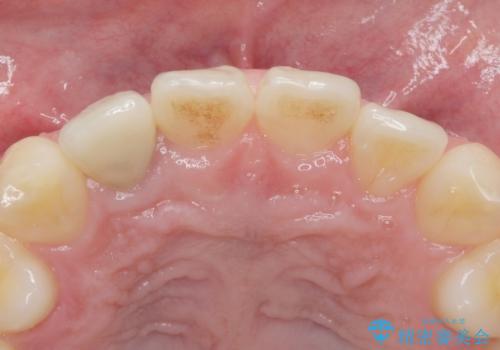

精査したところ、透過性のあるセラミッククラウンで治療されており、内側の黒い土台が透けてクラウンが黒ずんで見えていました。

土台を白いファイバーコアにやりかえたのち、土台の色を透過させないジルコニアフレームを用いたセラミッククラウンによる治療を行いました。